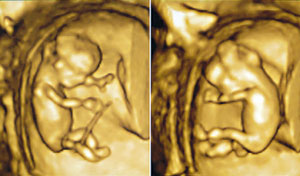

Istraživači sa Univerziteta Vašington u Sijetlu uspešno su sekvencionirali kompletan genom fetusa, koristeći isključivo DNK bebe iz krvi majke. Za razliku od ranijih metoda, ova je potpuno neinvazivna i ne stvara nikakav rizik za plod.

Već za pet godina ovaj test bi mogao da bude u kliničkoj upotrebi. Metoda bi pomogla da pre rođenja deteta roditelji znaju da li ono ima predispozicije za neke teške bolesti, kao i da li već ima neke deformitete. Ovaj test moći će najverovatnije da se radi u prvom tromesečju trudnoće, kada još nije kasno da se ona prekine, ukoliko plod ima ozbiljne deformitete.